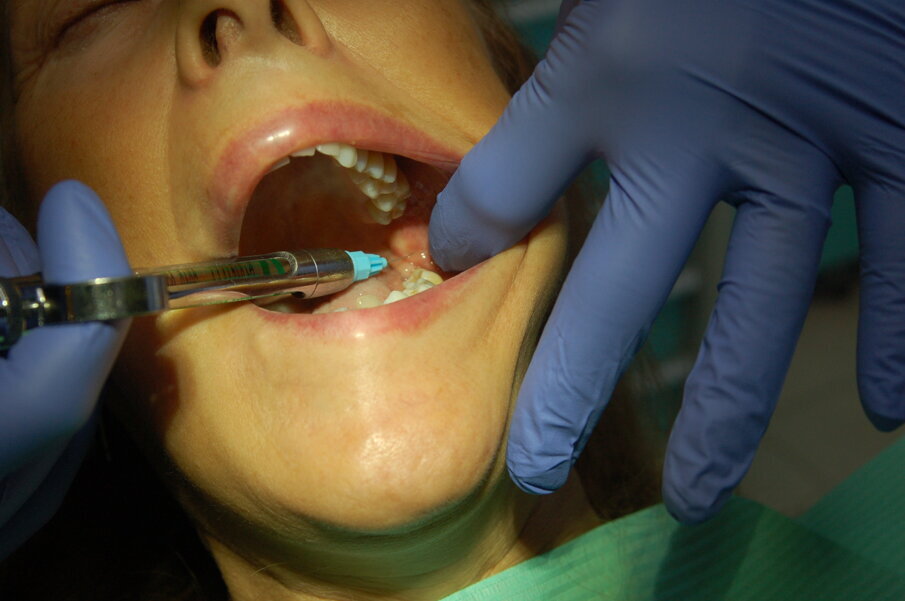

È quindi opportuno che un anestetico topico venga preliminarmente usato per rendere la fase di iniezione la meno sgradevole possibile, che l’iniezione venga eseguita applicando la giusta pressione, in modo da non sovradistendere i tessuti molli (una delle causa di dolore) e che sia fatta nel corretto sito anatomico (Figg. 1, 2). Il tempo di iniezione raccomandato è 1 ml/minuto. Tuttavia, l’84% dei dentisti inietta 1,8 ml in 20 secondi o meno. Inoltre la molecola opportuna per l’intervento programmato dovrà essere selezionata in base alla durata attesa della sua azione e, quindi, della sua efficacia, prestando attenzione anche alla quantità di vasocostrittore presente e alla condizione di salute generale del paziente.

Fig. 2 - Anestesia del nervo buccale.